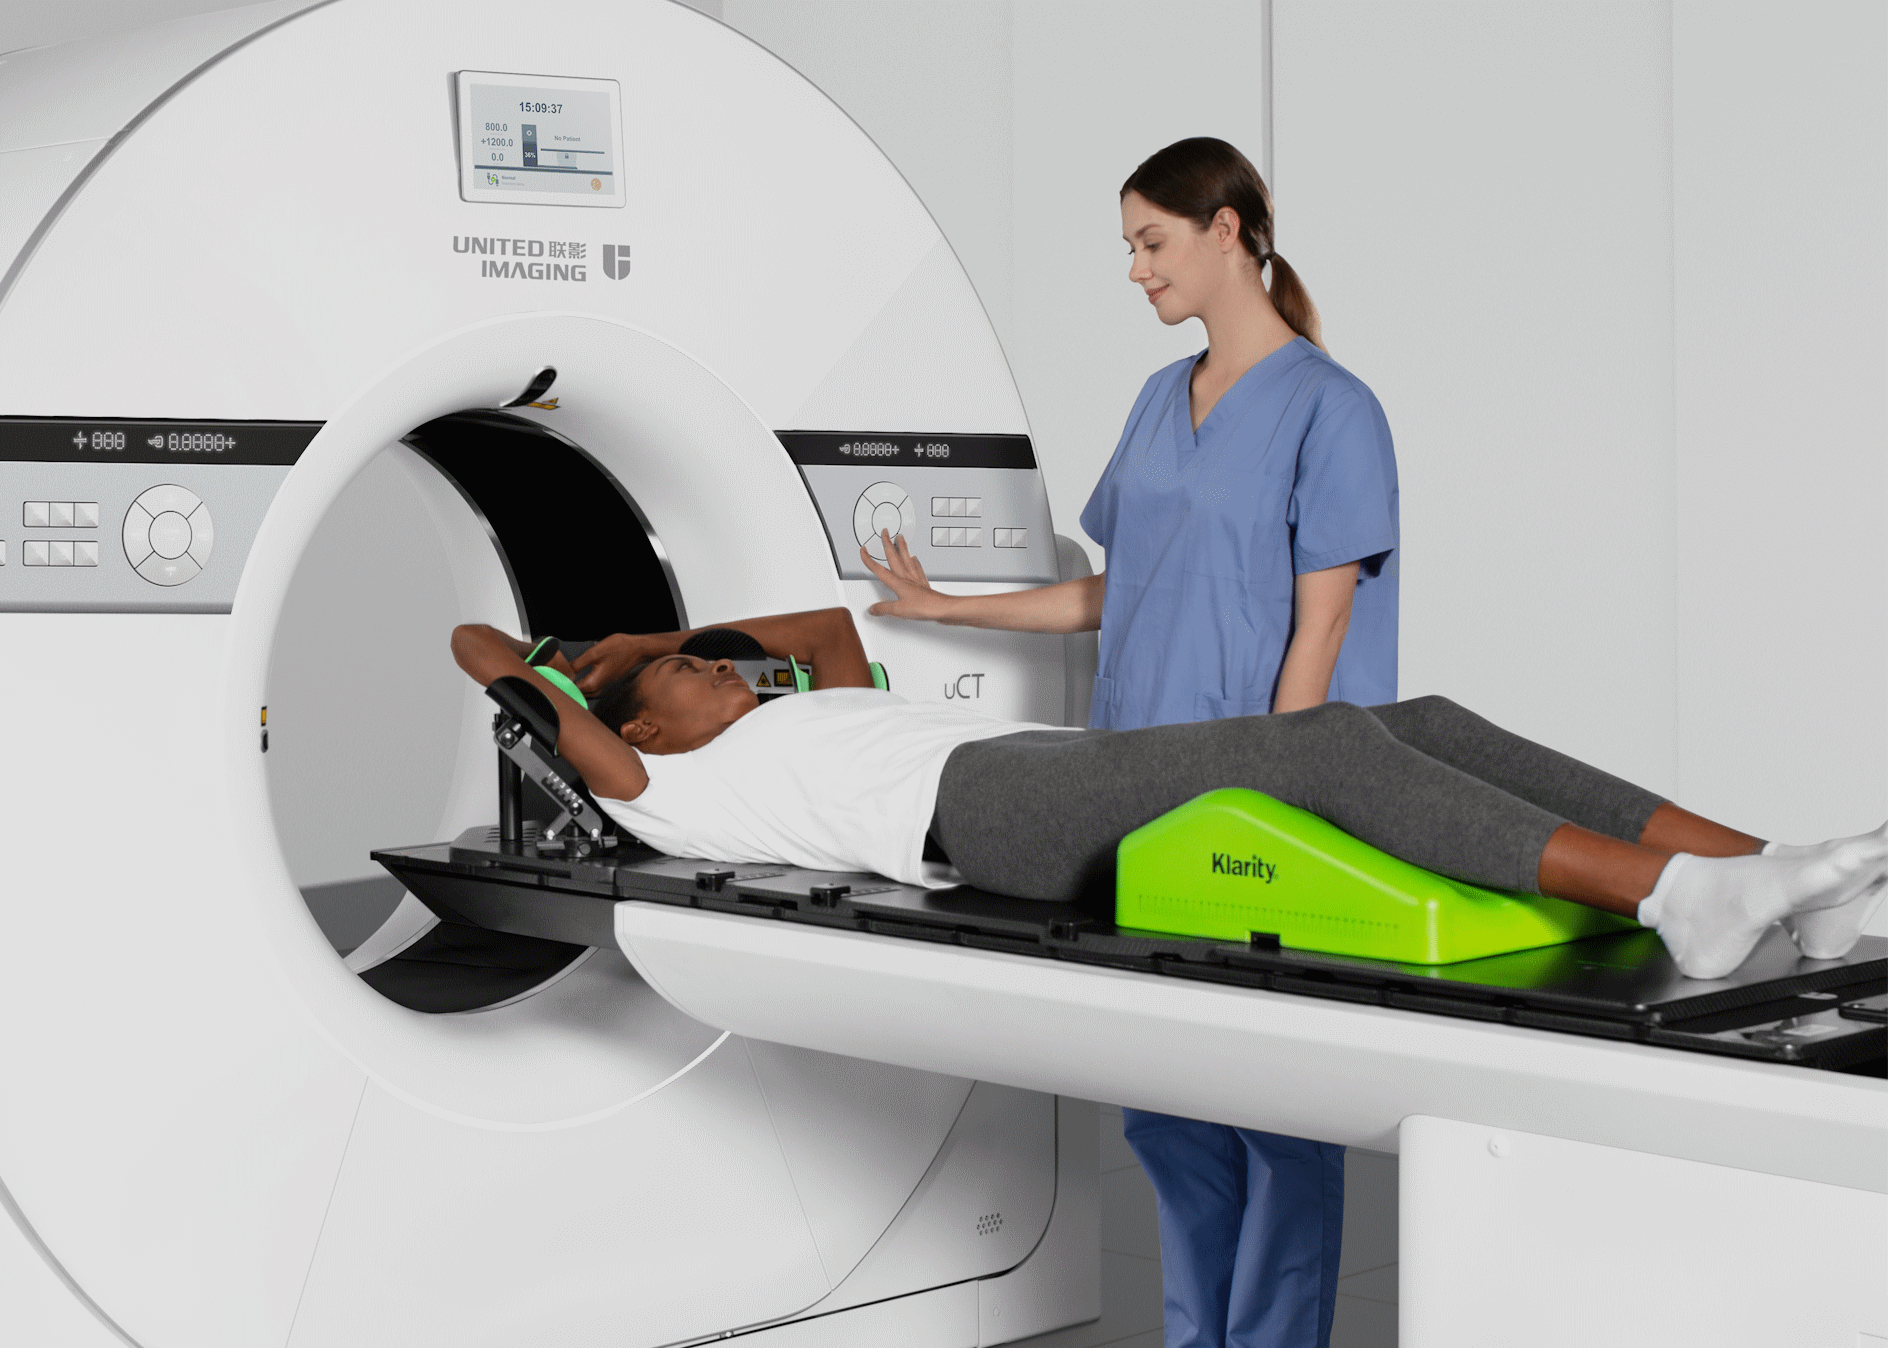

提供充足的患者摆位空间,支持放疗场景下容纳各类大尺寸定位附件;为介入影像引导手术提供更自如的操作空间

相较于常规CT系统,扫描视野提升26%*,对大体重、偏中心摆位等特殊患者模拟定位扫描呈现更加完整的解剖结构